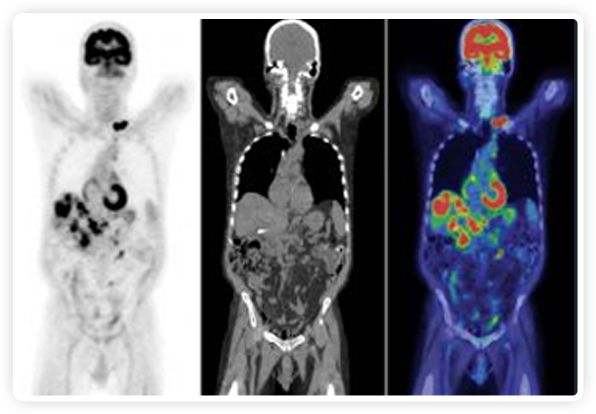

提起放療設(shè)備的引導(dǎo)系統(tǒng),大家通常會想到結(jié)構(gòu)性成像的CT或核磁。但你有沒有想過用功能性成像來引導(dǎo)放療呢?美國的一家醫(yī)療器械公司從2011年就致力于研究開發(fā)用PET提供生物學(xué)指導(dǎo)放射治療的設(shè)備BgRT。BgRT能實時利用癌癥的生物學(xué)特征作為信號指導(dǎo)治療全身腫瘤。

PET+放療共同治療

RefleXion將PET成像與立體定向放射治療相結(jié)合。在注射示蹤劑后,RefleXion的技術(shù)基于示蹤劑信號實時地在一個或多個目標(biāo)上引導(dǎo)治療性X射線。使用這種專有方法,RefleXion的平臺有可能比現(xiàn)有系統(tǒng)向癌癥病變提供更高劑量的輻射,并改善周圍健康組織的保護。